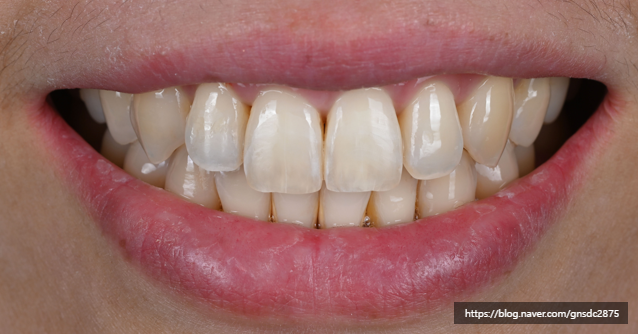

#CASE 02

백색반점이 있는 길이가 다른 앞니

다음 환자분도 양앞니의 백색반점과

미세하게 다른 치아 길이를

앞니통합치료 뉴티스로 개선하였습니다.